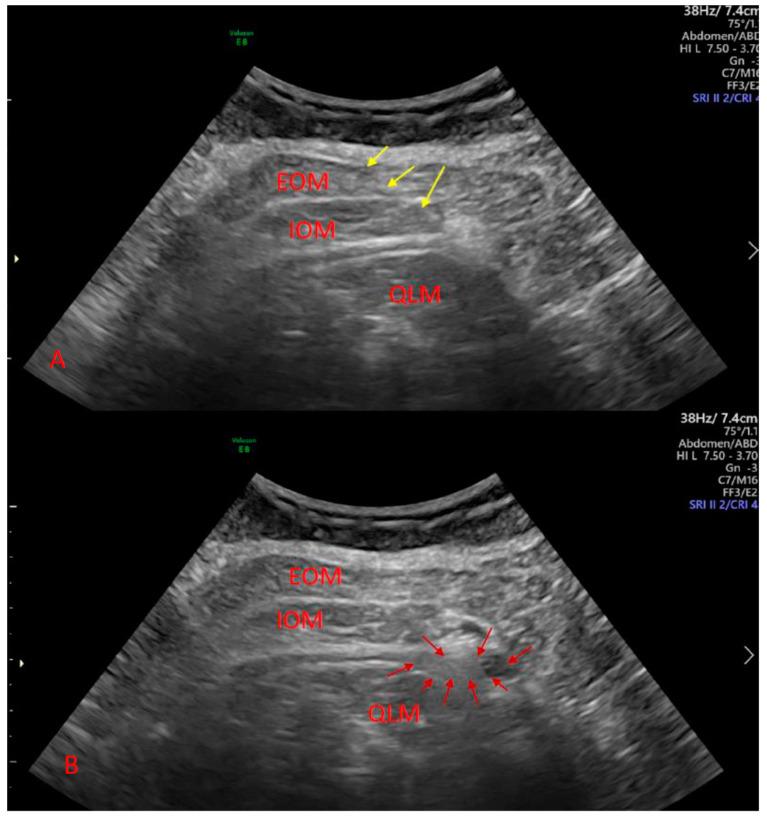

This study was a randomized, controlled trial of 105 patients conducted in two hospitals. All patients were anesthetized spinally for elective cesarean section. Each participant was randomly allocated to one of three study groups: the quadratus lumborum block (QLB) group, the transversus abdominis plane block (TAPB) group, or the control (CON) group. The primary outcome of this study determined acute pain intensity on the visual analog scale (VAS). The secondary outcomes determined morphine consumption and chronic pain evaluation according to the Neuropathic Pain Symptom Inventory (NPSI) after hospital discharge.

这是一项在两家医院进行的 105 例患者的随机对照试验。所有患者均接受脊髓麻醉行择期剖宫产。每位参与者被随机分配到三个研究组之一:竖脊肌阻滞(QLB)组、腹横肌平面阻滞(TAPB)组或对照组(CON)。本研究的主要结局是使用视觉模拟评分(VAS)确定急性疼痛强度。次要结局是根据出院后神经病理性疼痛症状量表(NPSI)确定吗啡消耗量和慢性疼痛评估。